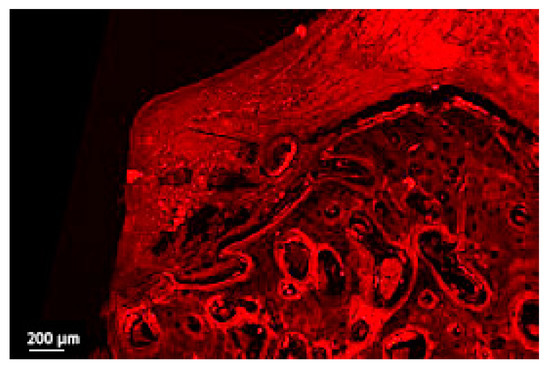

Figure 6.

Detail of the soft tissue bone in a thick section of a non-ligated implant. Note the ulcerated buccal pocket epithelium, the interrupted epithelial lining, the infiltration of inflammatory cells and the disruption of collagen network (implant #2, oral aspect; bar, 200 µm).

The usual light microscopy technique using pentachrome stains revealed good tissue morphology preservation; however, the opacity of the metallic implant made it difficult on some of the specimens to properly identify the implant shoulder. The CLSM thin sections were easier to scan, having a flatter surface, yet the grinding to a thin section led to minor tissue cracks in the bone component (Figure 3A,B). Furthermore, the use of mounting medium and coverslip on the thin sections induced an additional decrease in contrast, altering the quality of soft tissue morphology in the thin sections (Figure 3A,B). In both thin and thick sections, the implant shoulder was easily identifiable, except in the thick sections where the implant was lost during histological processing. The peri-implant sulcus is shallower in non-ligated specimens than in ligated ones, the bone is in contact with the implant surface and the soft tissue is in contact with the healing abutment (Figure 4). Infiltrated connective tissue (ICT) was present in contact with bone and implant (Figure 5). However, it is important to mention that the cellularity of the ICT was not visible under CLSM; therefore, LM seemed better suited for the assessment of the ICT. Epithelial lining integrity was broken, more pronounced on the oral aspect, making the identification of landmarks like aJE extremely difficult (Figure 6). This comes not as a surprise under the severe inflammation circumstances found in peri-implantitis, as this landmark is poorly identifiable even on LM. In these areas of integrity loss, the highly inflamed soft tissue was identified in direct contact with the bone and implant (Figure 7). Regarding the soft tissues, the epithelial covering is clearly identifiable on both types of evaluation (LM and CLSM).

There are several advantages of CLSM over LM, as a good method to identify both soft and hard tissue modifications, especially when analyzing thicker sections, that tend to appear opaque in LM: there are no laborious staining protocols because CLSM uses intrinsic fluorescence; the “thick” sections can be easily manipulated by hand; it can provide 3D reconstructions. Particular disadvantages of CLSM when compared to LM resulted from the observation of this study: the ICT, a relatively important area when describing the inflammation in peri-implantitis, cannot be identified neither characterized properly without supplementary fluorescent labelling (Figure 7), same for the limit of the squamous epithelium (aJE) that did not appear clearly visible on many sections (Figure 6).